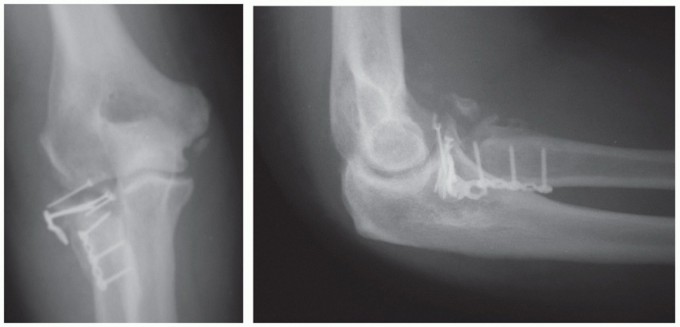

Serial x-rays are obtained to detect any loss of reduction at immediate postoperative, 2 weeks, 6 weeks, and 3 months, until healing is achieved (FIG 12).

- FIG 12 • Postoperative x-rays showing anatomic reduction of the radial head fracture. The Biotrak screws are radiolucent. Note that anchor holes are seen at the crista supinatoris where the lateral ulnar collateral ligament (LUCL) and annular ligament complex are repaired.

Symptomatic hardware may require secondary removal (FIG 13). Infection

FIG 13 • A. Oblique radiograph demonstrating prominent hardware limiting forearm rotation. B.*

Arthroscopic view in the lateral gutter demonstrating hardware impingement at the PRUJ.